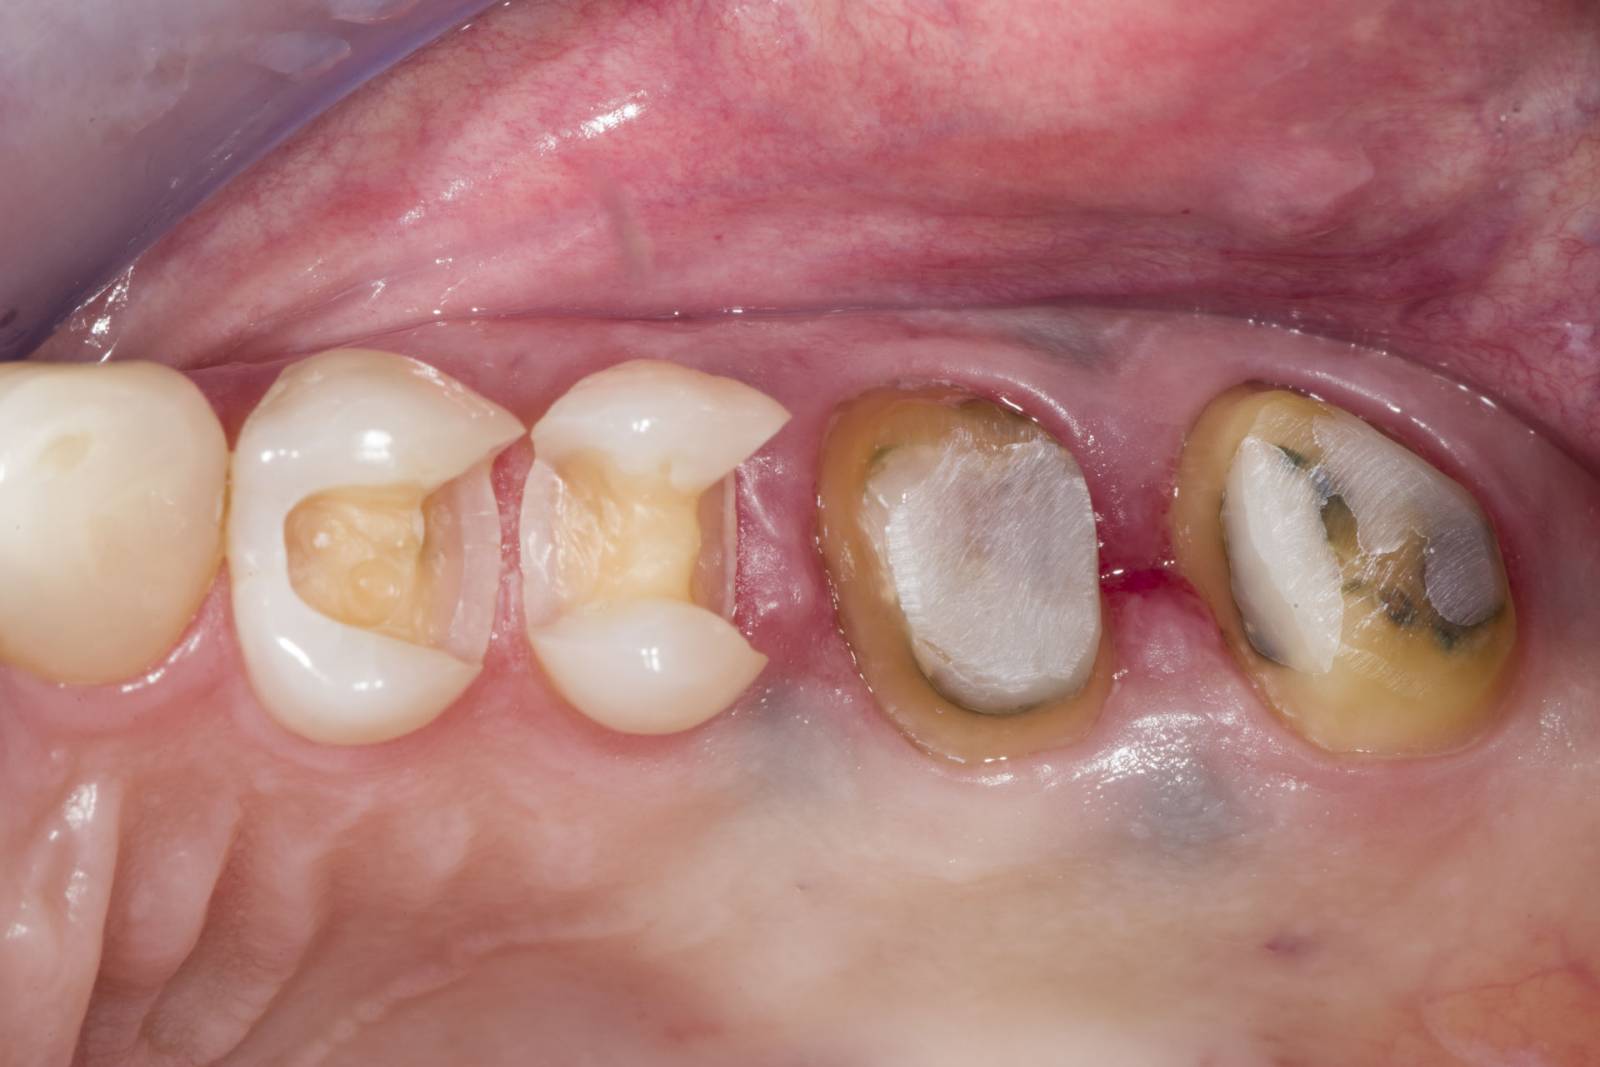

Before: Fractured metal-ceramic crown on tooth 14, which had previously been treated endodontically.

After: Translucent full zirconia crown for an esthetic result with maximum resistance and retention shape.